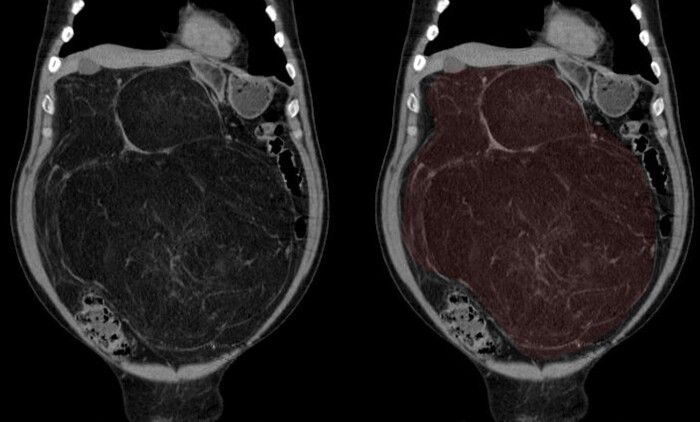

Было проведено КТ-обследование органов брюшной полости, где обращало на себя внимание необъятное объёмное жиросодержащее образование в забрюшинном пространстве с эпицентром справа, заполняющее собо практически весь живот:

Образование (красным) охватывало со всех сторон правую почку (голубым):

И имело солидный компонент:

Признаков инвазии (прорастания) в окружающие органы не было.

Согласно радиологической картине был выставлен предварительный диагноз забрюшинной липосаркомы.